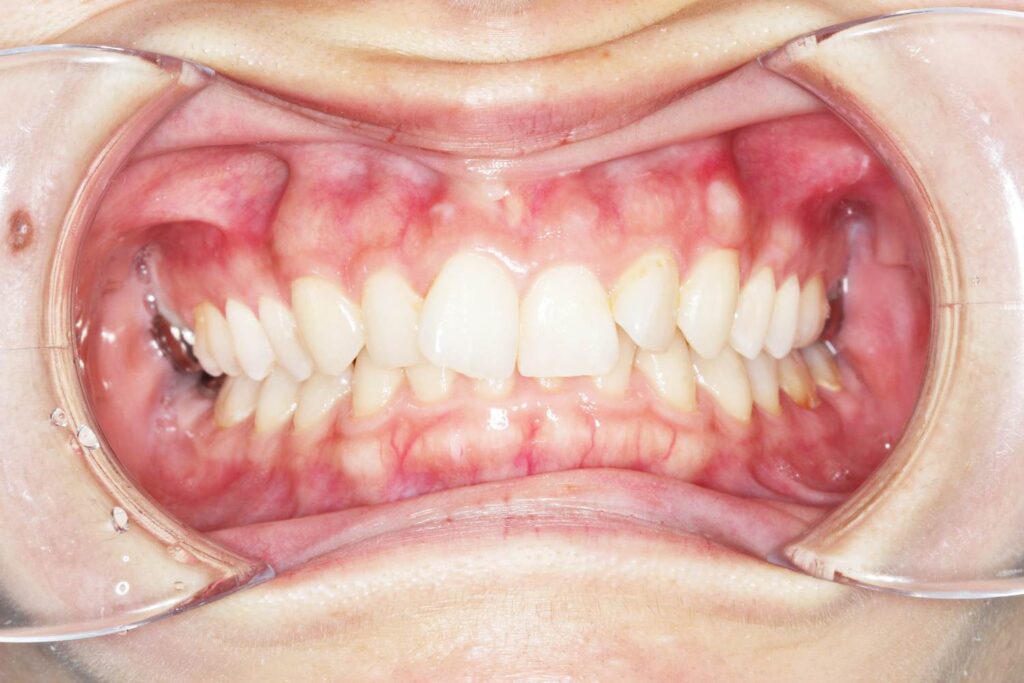

Before

After

年齢 10代

治療装置 上は裏側の矯正装置(ハーフリンガル)

治療内容 上下左右4本抜歯

治療期間 2年8か月

リスク 歯の移動に伴う痛み、歯肉退縮、歯根吸収、歯肉炎、虫歯

主訴 八重歯が気になる

症状 叢生(ガタガタ)

治療回数 33回程度

総額費用 125万円程度